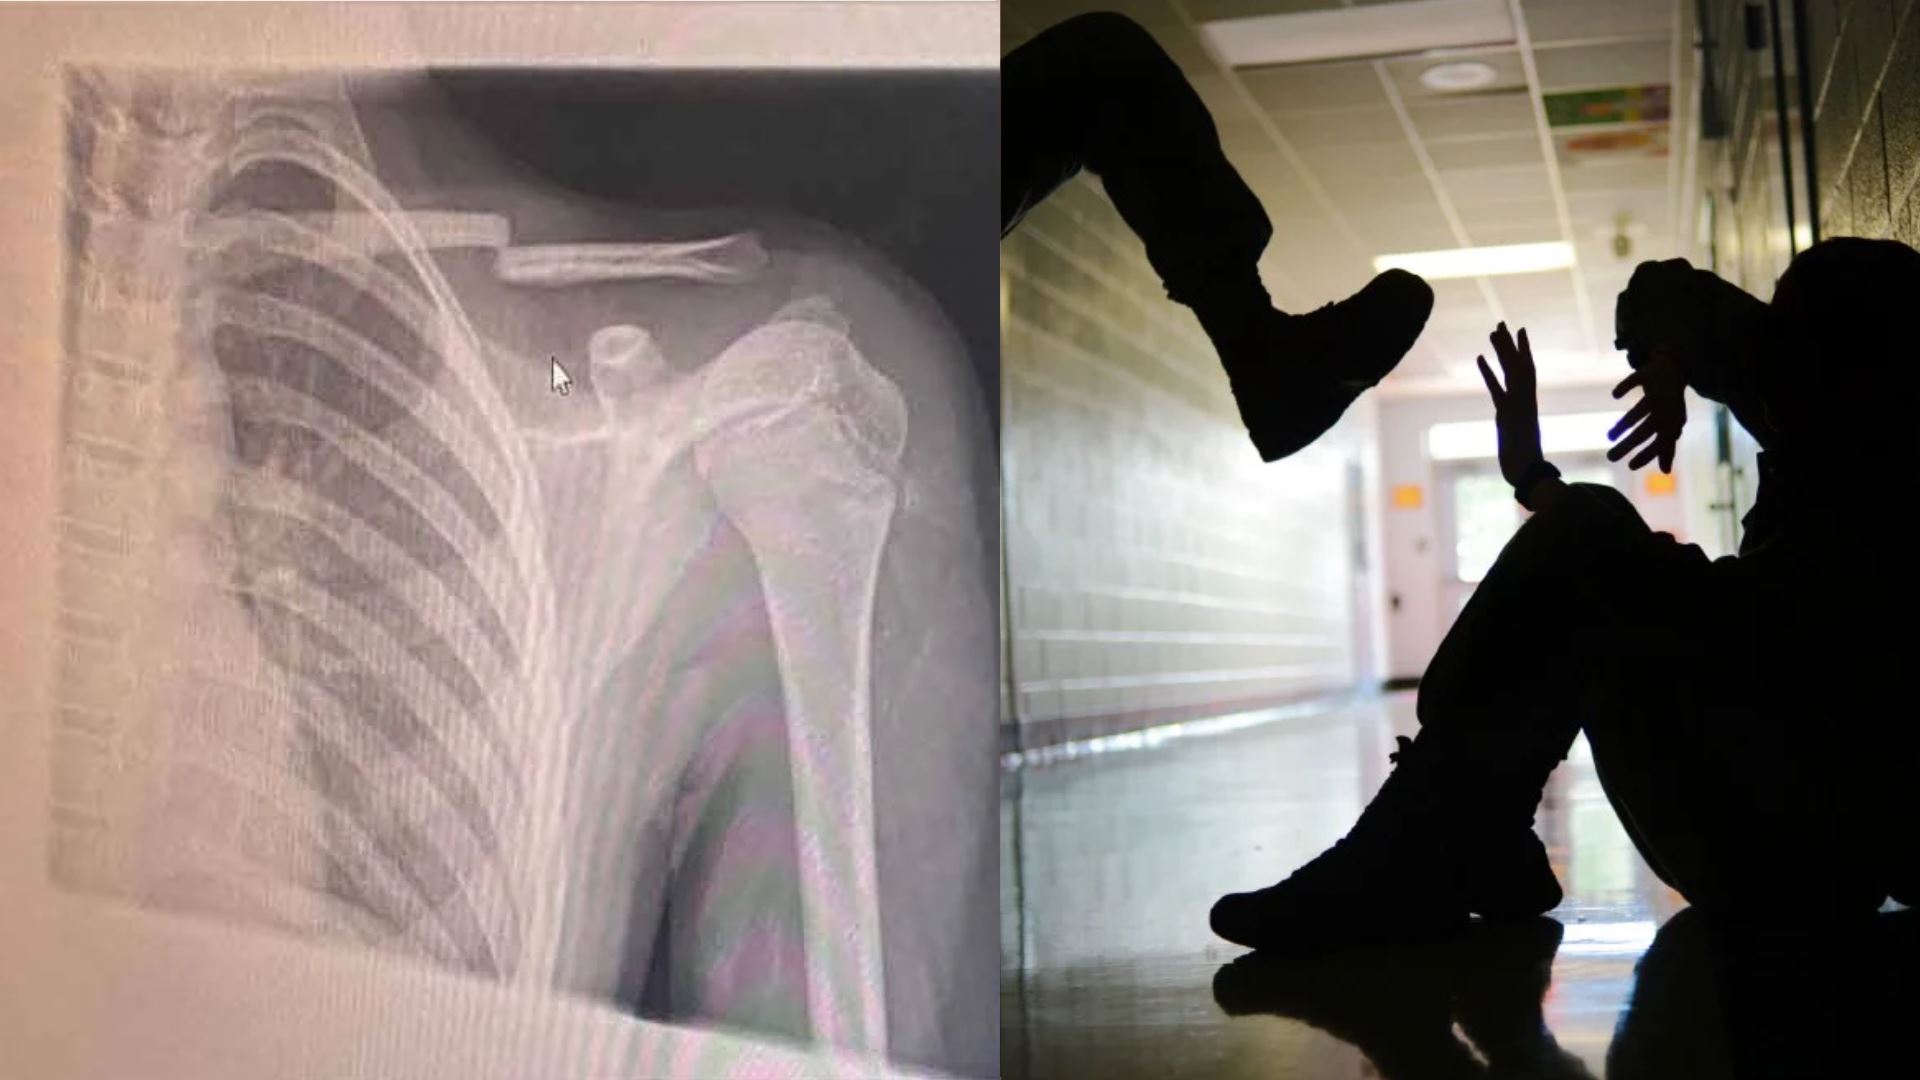

Murid Cedera Patah Tulang Selangka Akibat Buli di Sekolah

murid cedera patah tulang selangka akibat buli di sekolahFoto: Sinar Harian

Seorang kanak-kanak lelaki berusia 12 tahun mengalami kecederaan serius apabila tulang selangkanya patah selepas terjatuh akibat ditolak dalam satu kejadian buli di sebuah sekolah rendah agama di sini.

Menurut Nina, kejadian bermula sebaik selesai solat Asar di surau sekolah apabila beberapa murid menarik tikar sejadah hingga menyebabkan anaknya hilang imbangan dan terjatuh. Jatuhan tersebut begitu kuat sehingga mengakibatkan tulang selangka anaknya patah.